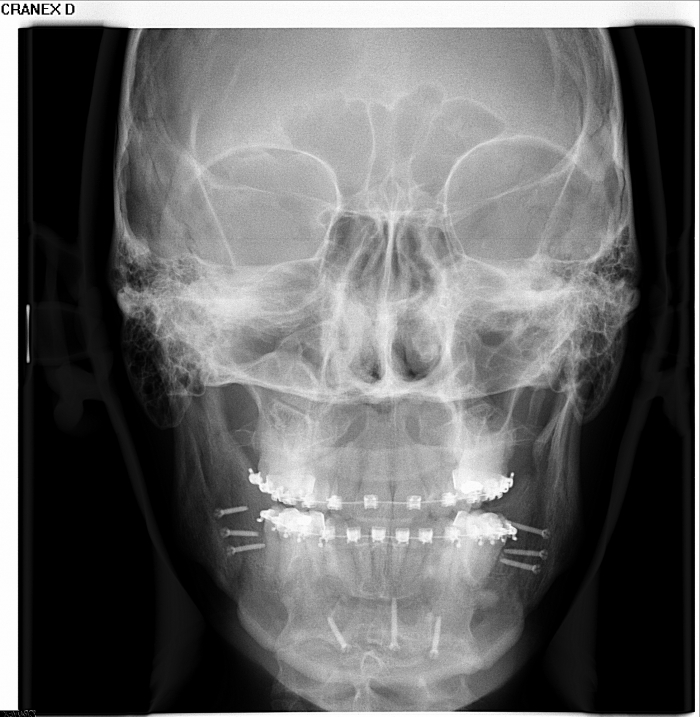

Telerradiografia frontal após cirurgia realizada em 2015 - Clínica Cliniface

Telerradiografia frontal após cirurgia realizada em 2015